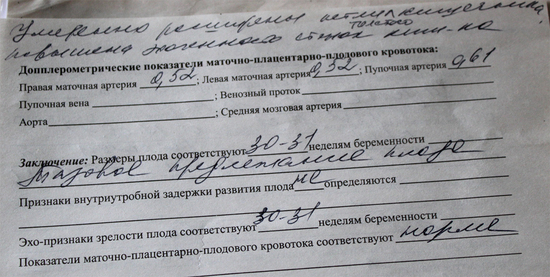

Растроили проблемы с кишечником немного - написано "Умеренно расширены петли толстого кишечника", врач сказала надо провести профилактику инфекции, мне уже выписали свечи в ЖК. А так все опасения не оправдались слава Богу!

губки бантиком!Растроили проблемы с кишечником немного - написано "Умеренно расширены петли толстого кишечника", врач сказала надо провести профилактику инфекции, мне уже выписали свечи в ЖК. А так все опасения не оправдались слава Богу!